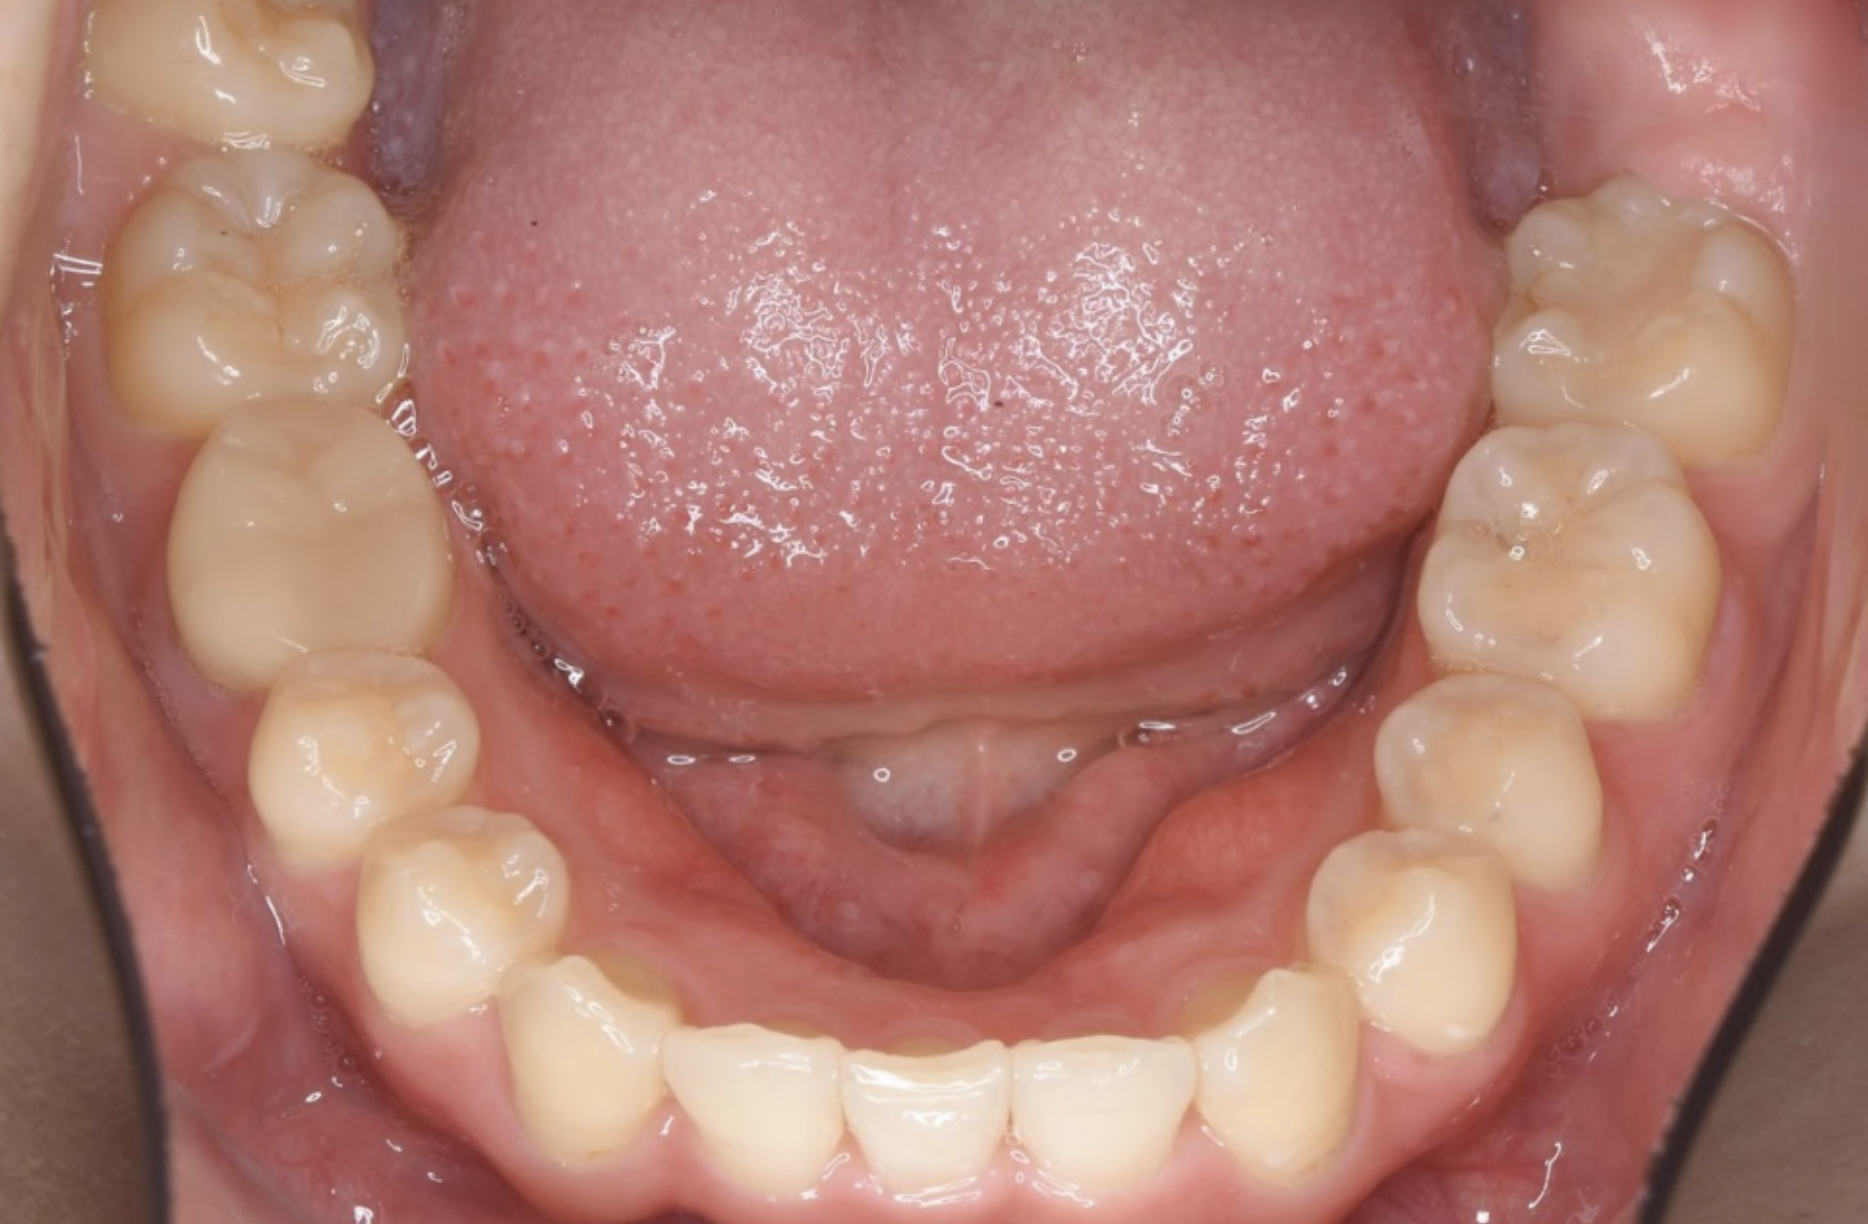

治療後の口腔写真

After

右上側切歯(2番)が欠損している症例でしたが、患者様との相談の上で、無理に2番目の歯の形を再現せずに今ある歯の形で綺麗に並べる方針をとりました。

左右を完全に対照的にしなくとも、綺麗な仕上がりというのは作ることができ、「自然である」ことがかえって違和感のない仕上がりになることもあります。